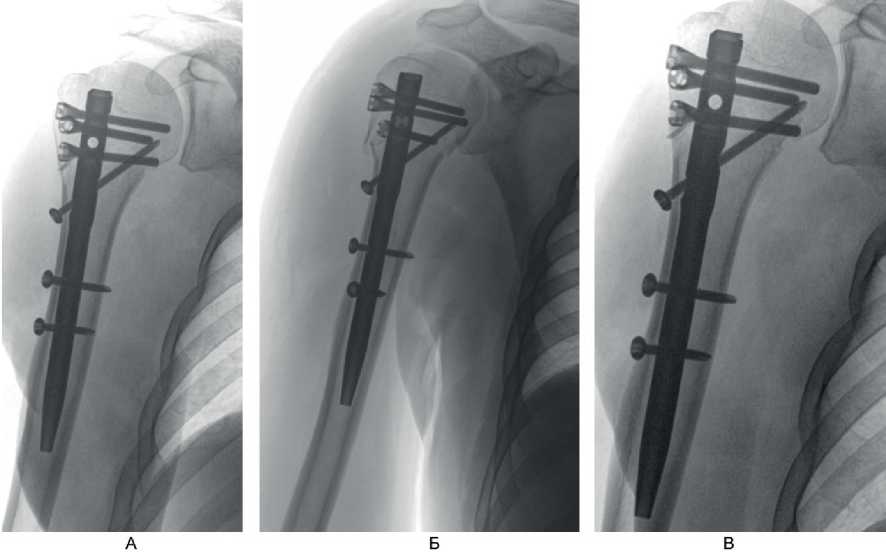

Рис. 5. Этапы репозиции отломков и установки интрамедуллярного штифта при переломах типа Б по АО. А – прошивание сухожилий манжеты ротаторов с костными отломками; Б – репозиция и временная фиксация отломков тонкими спицами Киршнера, установка направляющего устройства для вскрытия интрамедуллярного канала плечевой кости; В – установка интрамедуллярного штифта в плечевую кость

Перелом по классификации АО – С3.1. На 2-е сутки после поступления выполнено оперативное вмешательство – БИОС хирургической шейки правой плечевой кости. Рентгенография на 1-е сутки после операции представлена на рис. 9А, Б, контрольная рентгенография плечевого сустава через 6 мес после операции – на рис. 9В. Функциональный результат после операции – на рис. 10.

Рис. 9. Больной А., 50 лет. А, Б – рентгенография на 1-е сутки после операции; В – через 6 мес после операции